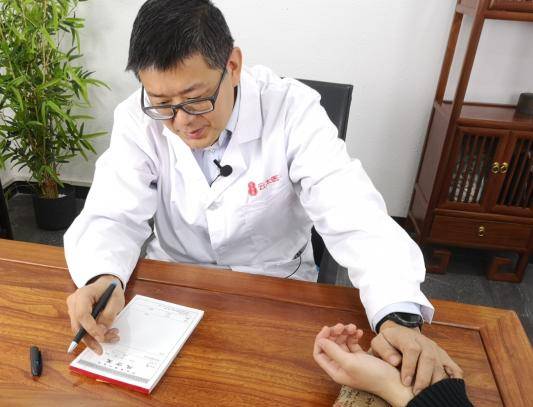

素朴中医院杜云江:想要更好的生活质量,能保髋就不要置换!

杜云江从事骨伤科诊疗工作近20年,始终坚守在临床一线,在跟患者相处中他越来越能感受到治病救人的意义。他说:“我这辈子,就是专注治疗骨病,连晚上睡着了,梦里还在和病人交流病情。”一心一意致力于骨病患者的治疗,就是杜云江作为一名中医医者的仁心。

在治疗过程中,杜主任会根据患者的具体情况,如观面色、看舌质、询问病情病史等,进行精准辨证。对于气血两亏、肾气不足的患者,会特别注重益气补血填精的治疗原则,以确保治疗方案的针对性和有效性。